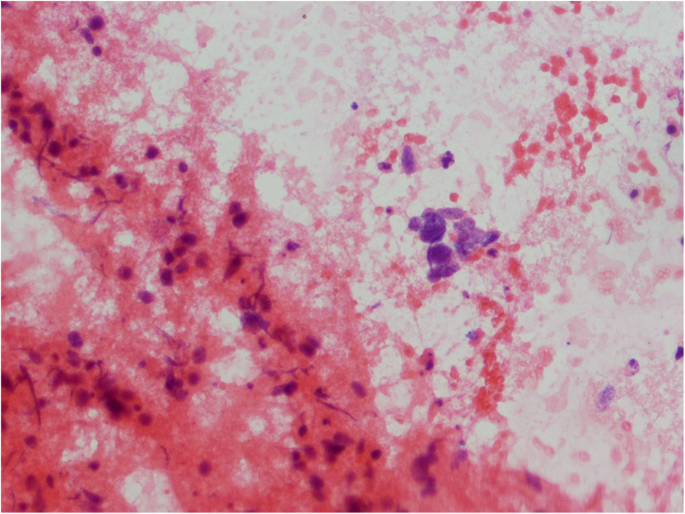

Ultrasound revealed an unchanged right thyroid lobe, while the left lobe was significantly enlarged (44 × 61 × 100 mm) and almost completely filled by a heterogeneous tumour 44 × 55 × 70 mm, with numerous calcifications, almost completely without vascularisation (Fig. 1). The tumour infiltrated adjacent thyroid tissue, which could give an image similar to hypoechoic areas in the SAT, but the features of superficial neck muscle infiltration were also visible (Fig. 1). No pathological lymph node was revealed in US. Tumour FNAB revealed epithelial cells with eosinophilic cytoplasm and nuclei located at one of the cytoplasmic poles, showing distinct anizocytosis, anizocoria and heterochromasia (Fig. 2). Cytological diagnosis was non-small cell cancer. Neck and chest computed tomography (CT) revealed a large tumour of the thyroid, with visible compression and displacement of the trachea (Fig. 3), as well as numerous tumours of size up to 35 mm within both lungs (most likely metastases), without a clearly evident primary lesion. The patient was referred to the oncology clinic, where - after confirmation that the thyroid tumour is a metastasis of non-small cell lung cancer (NSCLC), the patient was qualified for palliative radiotherapy. In the meantime, the patient started suffering from dyspnoea.. The patient died 2 months after the correct diagnosis was established. Initial SAT diagnosis delayed treatment for about a month which is a dramatic waste of time in the case of NSCLC.